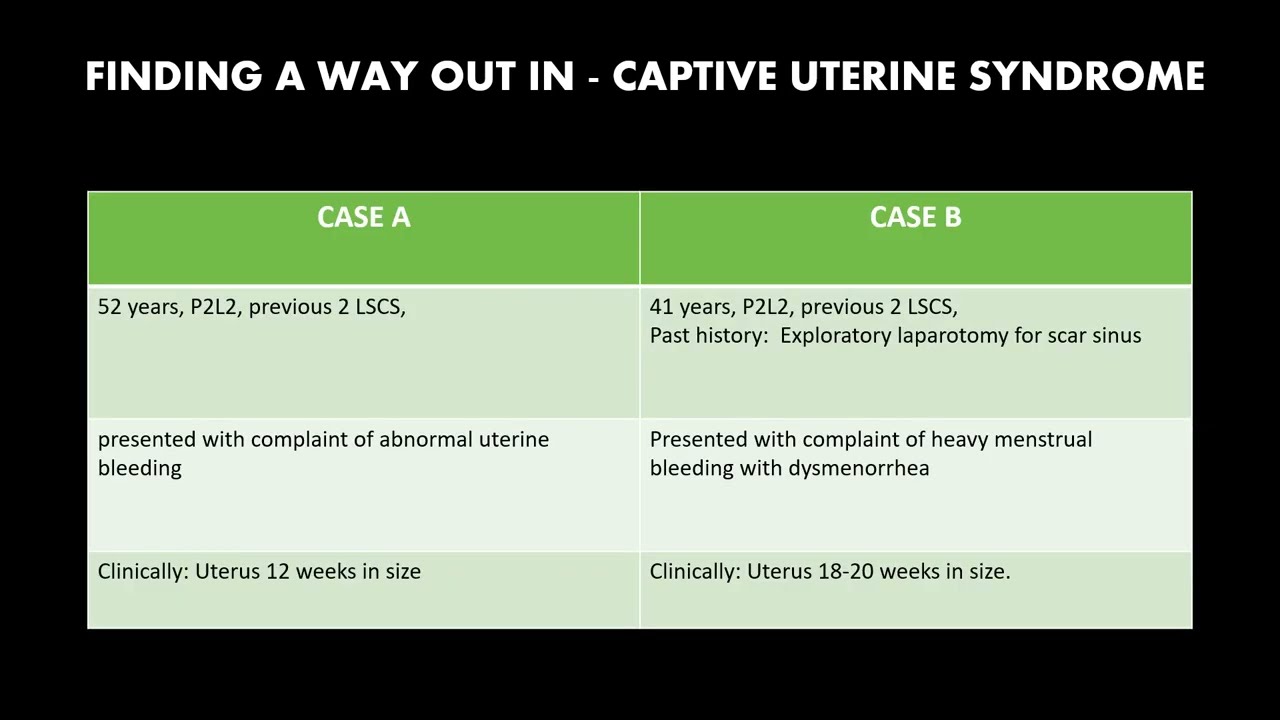

#253 Finding a Way Out in Captive Uterine Syndrome- Dr. Rohit Raina

KS Awards, Robotics, Surgeon ';